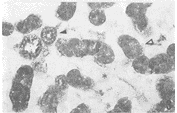

1.阴性对照结果显示为阴性。阳性对照结果显示小肠壁内有丰富的SOM、SP、VIP及NPY免疫反应纤维和细胞。在大鼠颌下腺的HE染色切片中,可见混合性腺泡和各级导管,其中GCT粗长而弯曲,构成导管系统中重要组成部分。在免疫组织化学染色切片中,SOM、SP、VIP和NPY免疫反应性细胞呈浅棕色至深棕色不等,背景几乎无色。大鼠颌下腺GCT细胞分别呈SOM、SP、VIP和NPY免疫反应性,免疫染色产物分布于细胞质内,细胞核为阴性(图1~6)。此外,纹状管上皮细胞亦呈SOM、SP、VIP和NPY免疫反应性。

图1示大鼠颌下腺颗粒曲管细胞(△)呈SOM免疫染色阳性,腺泡细胞为阴性(*)。×200

Fig1The GCT cells(△) showing SOM-immunoreactivity,acinar cells(*)negative.×200